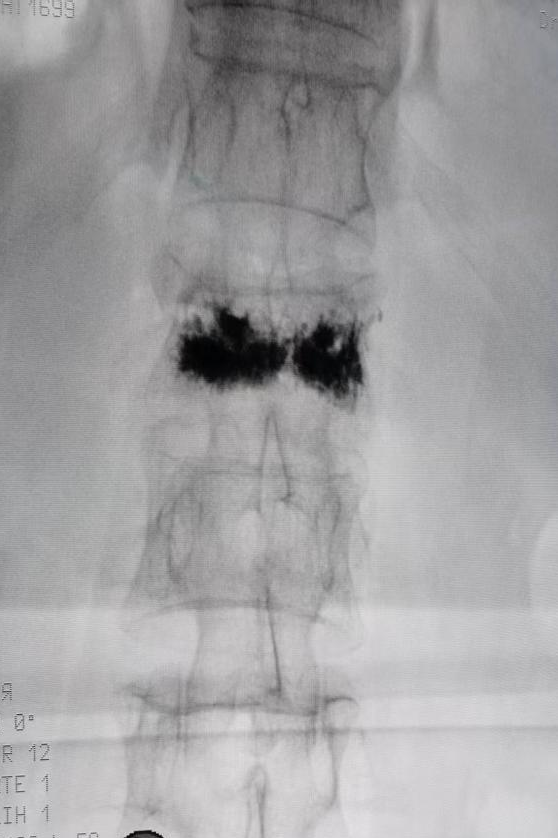

第1腰椎骨折术后正位X线片、侧位X线片,椎体黑色部分为手术注入的骨水泥